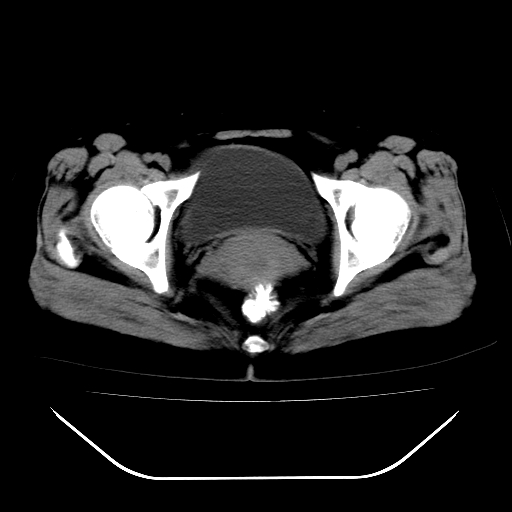

标题: CT28584:女,48岁,肛门坠胀感一年,肠镜未见异常。 [打印本页]

女,48岁,肛门坠胀感一年,肠镜未见异常。

子宫明显增大,形态不规则。多考虑:子宫肌瘤!

子宫明显增大,形态不规则,  盆腔积液 结合临床考虑:1子宫肌瘤, 2  盆腔炎。

道格拉斯窝积液考虑慢性盆腔炎,宫腔少量积液,子宫肌瘤不好说,建议增强。